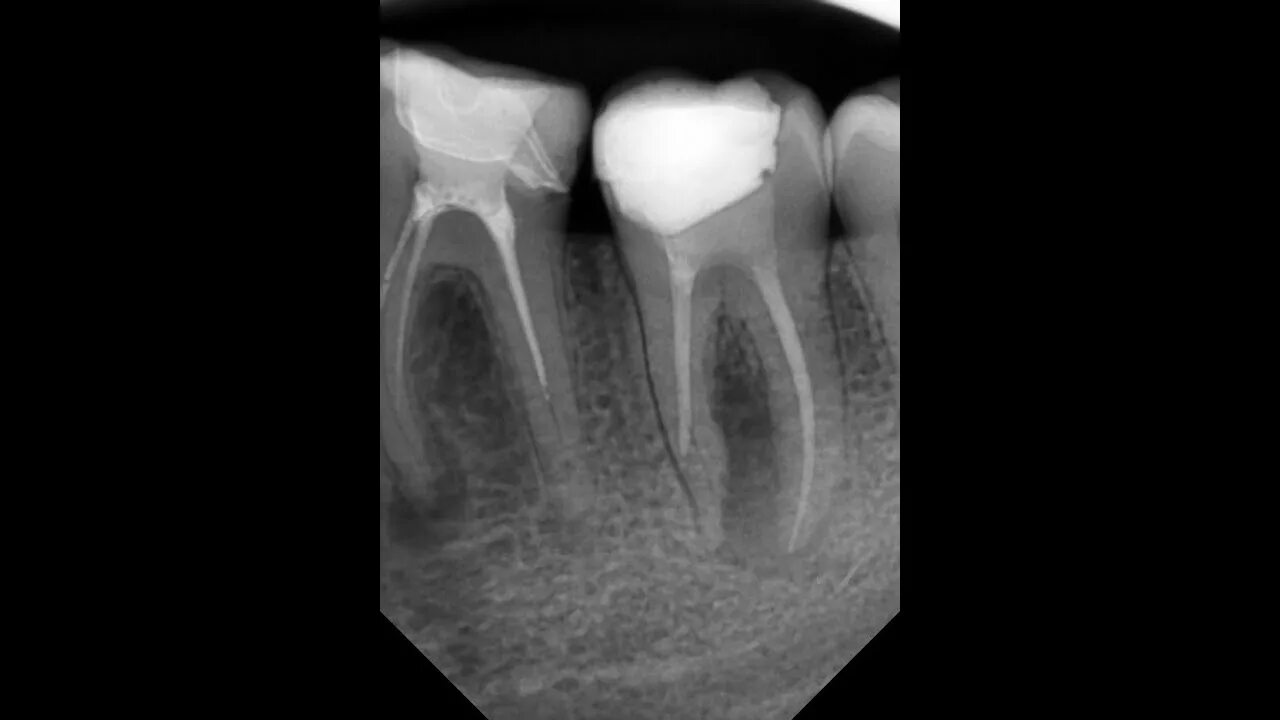

Пломбирование перфорации